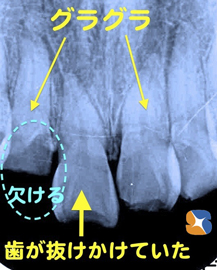

事故で前歯がグラグラ抜けかけ

コラム「事故で前歯がグラグラ抜けかけ」の画像